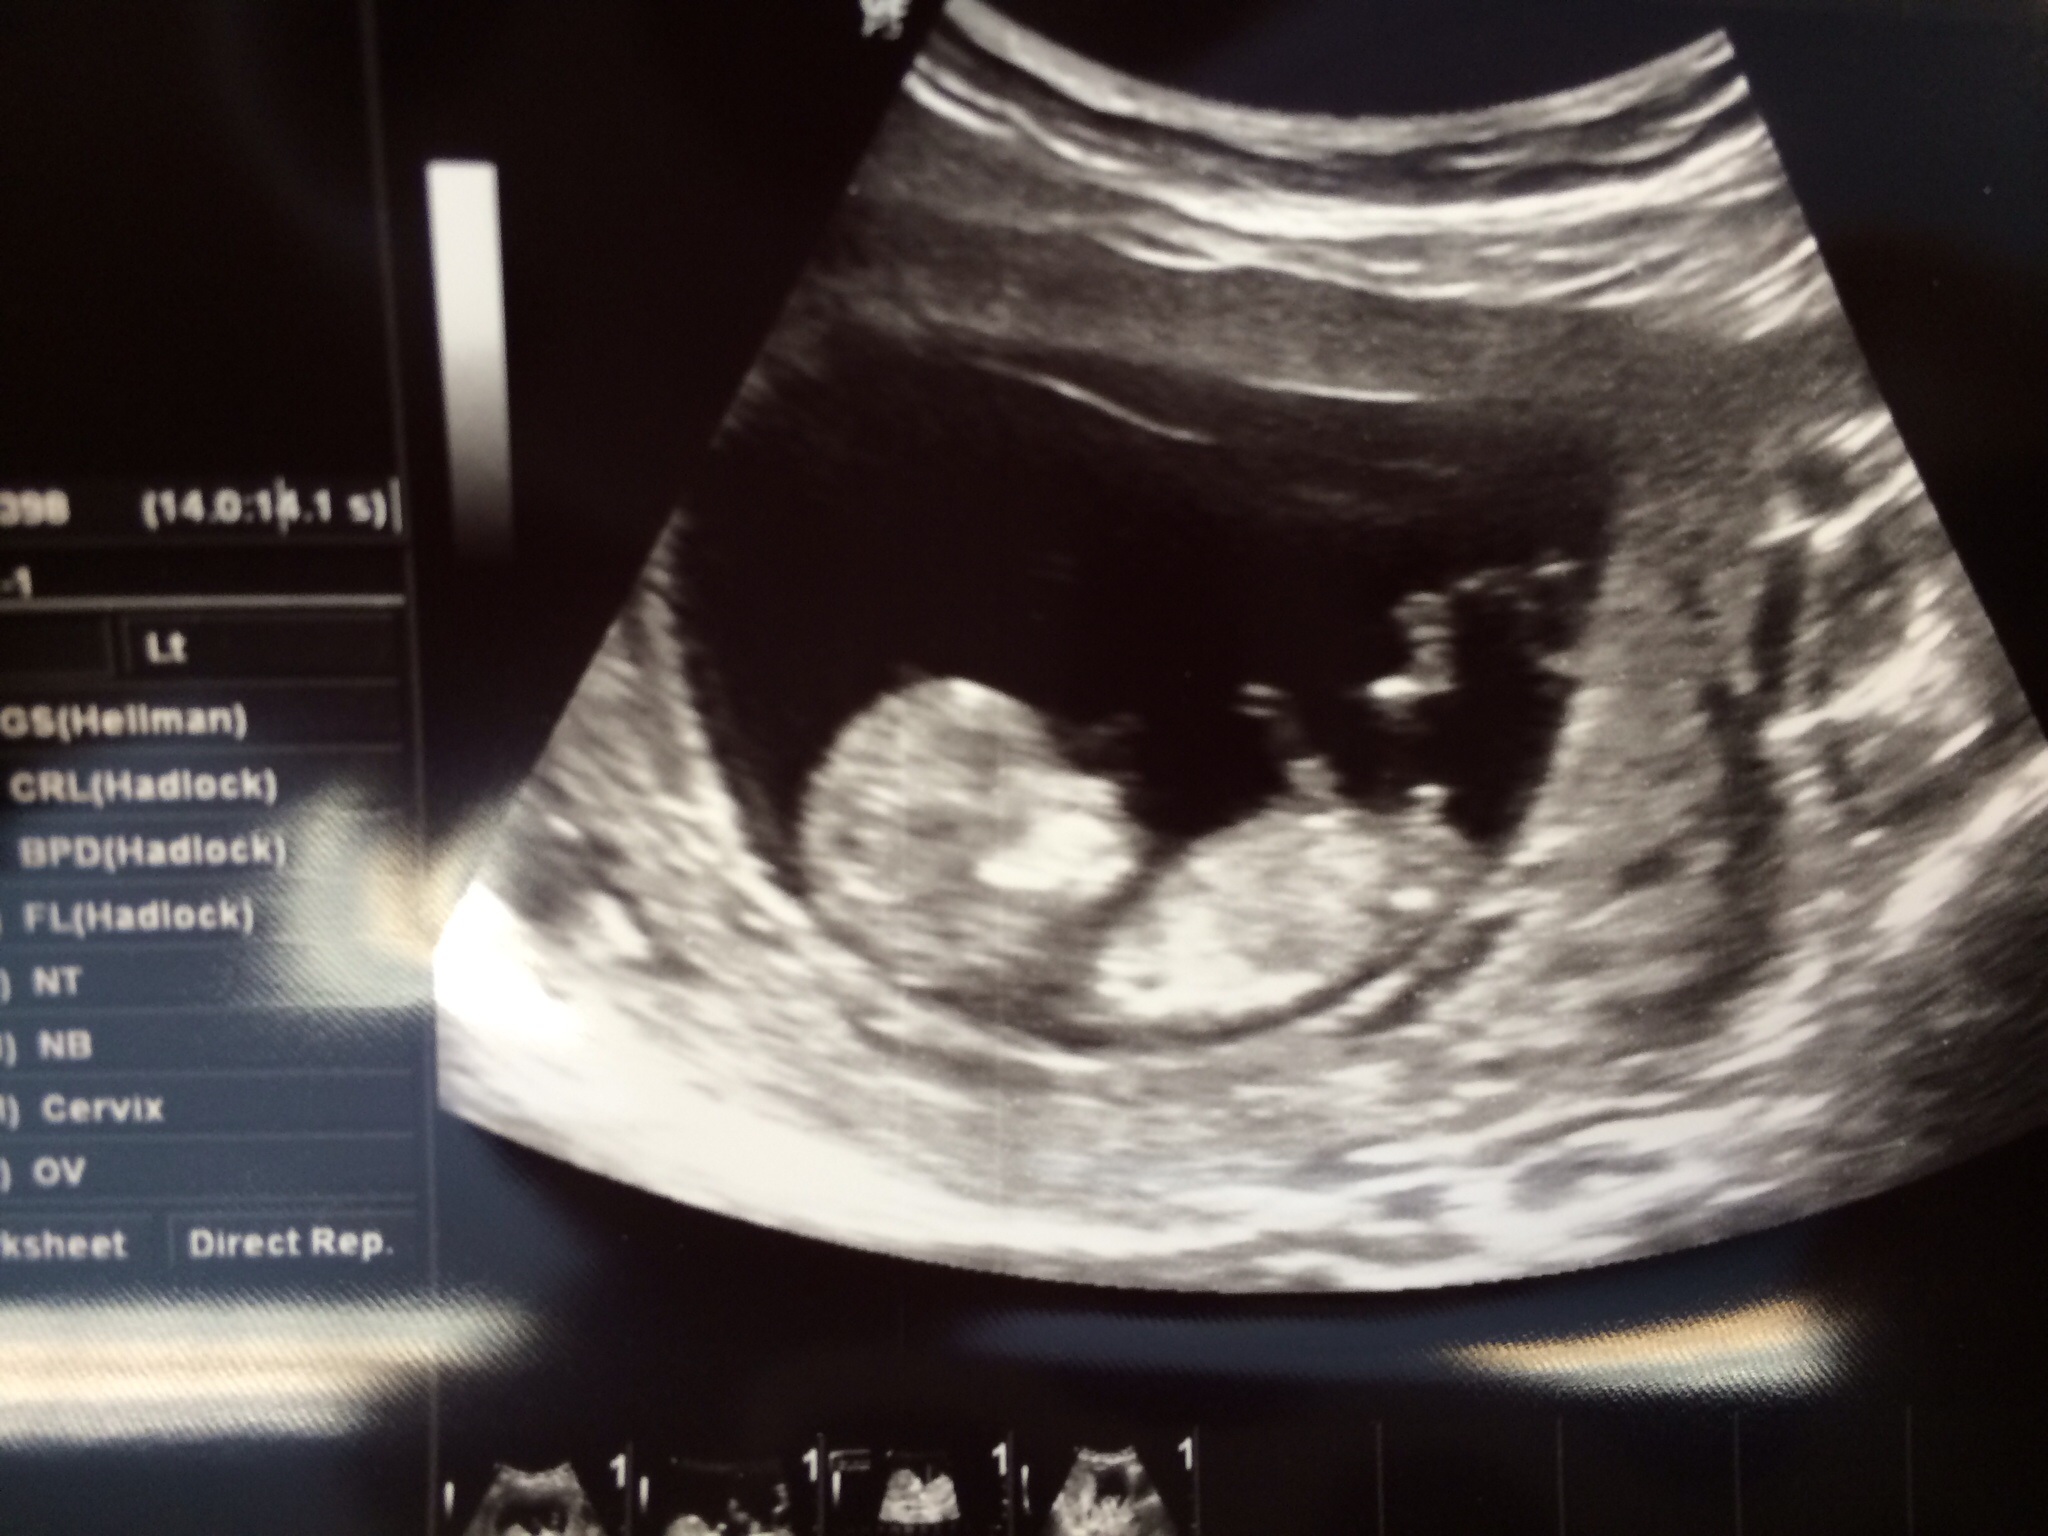

Boy

Boy!!

Baby boy :)

Look very boy to me.

Looking very boy there :-)